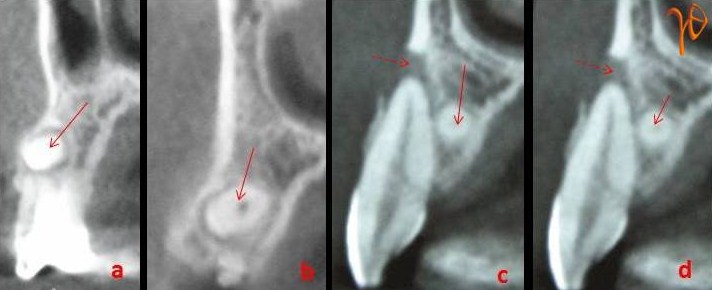

Εικ. 3 : Σε εγκάρσια τομή υπολογιστικής τομογραφία(CBCT) απεικονίζονται με ακρίβεια οι τοπογραφικές σχέσεις του υπεράριθμου με τα παρακείμενα δόντια.

Εικ. 4: Στις κάθετες τομές της υπολογιστικής τομογραφία(CBCT) απεικονίζεται με ακρίβεια η κατεύθυνση του υπεράριθμου (συμπαγές βέλος) και η ακρορριζική λύση του χειλικού οστικού πετάλου (διακεκομένο βέλος).